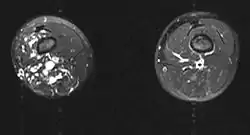

![]() صورة بالرنين المغناطيسي صورة بالرنين المغناطيسي | |